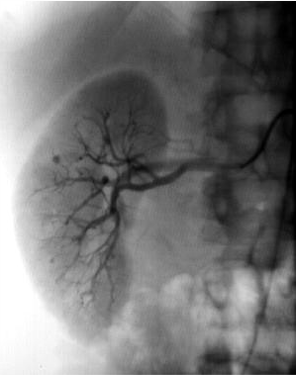

polyarteritis nodosa(PAN)

multiple small aneurysms in the right renal arterioles

this is an Aunt Minnie and diagnostic of PAN

associated with HBV and HCV